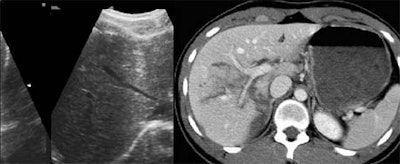

However, for visceral injury without free fluid, ultrasound was only 41% sensitive and 92% specific on the first pass. By the second exam, sensitivity had risen to 51% and specificity to 100%. A quarter of the organ injuries seen on CT did not have free fluid; therefore the first ultrasound missed 73% of these parenchymal injuries, Poletti said.

![]() |

"Ultrasound was very sensitive and specific [for detecting] free fluid when compared with CT results. However, it was very poor for showing parenchymal injuries... Twenty-five percent of the patients had visceral injuries with no associated free fluid," Poletti said. "Therefore, ultrasound is limited by the high amount of organ injuries that are not associated with free fluid."